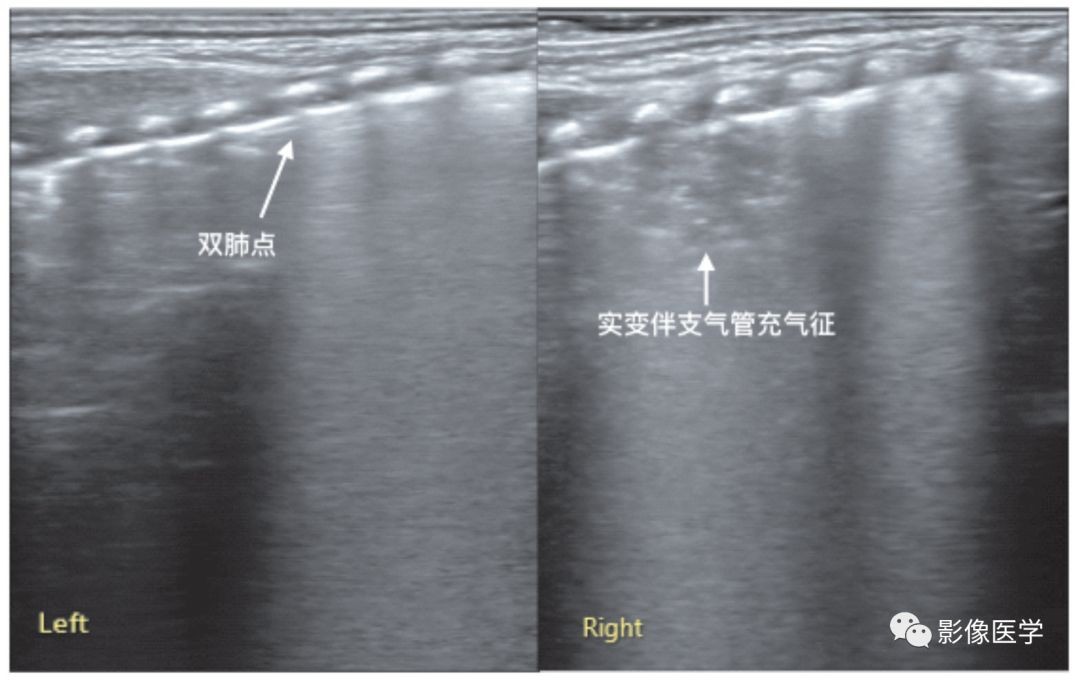

图6-20 乳汁吸入性肺炎:双肺点

胎龄32周,出生后28d,因胃食管反流致乳汁吸入。肺脏超声显示右肺明显实变伴支气管充气征,实变区边缘不规则,胸膜线消失或模糊;左肺未见实变,但可见明显双肺点(参见图6-21)。

图6-21 感染性肺炎:双肺点

胎龄31周,出生后20d,院内感染性肺炎。肺脏超声显示左肺呈双肺点征象、右肺大面积实变伴支气管充气征。结合上例,说明在肺炎(吸入性或感染性)时也可以见到双肺点,再一次证明双肺点并不是湿肺的特异性征象,任何肺部疾病,当引起上下肺野病变程度不一致或性质不同时,均可以出现双肺点征象。